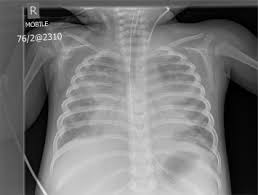

El síndrome de dificultad respiratoria aguda pediátrico (SDRAP) es una condición potencialmente mortal caracterizada por la aparición aguda de insuficiencia respiratoria hipóxica con infiltrados bilaterales, en ausencia de causa cardiogénica. Puede progresar de síntomas leves a fallo respiratorio grave en cuestión de horas.

Los criterios diagnósticos clave, según las guías PALICC-2, incluyen:

• Inicio agudo dentro de la semana posterior a un insulto clínico conocido

• Infiltrados bilaterales […]